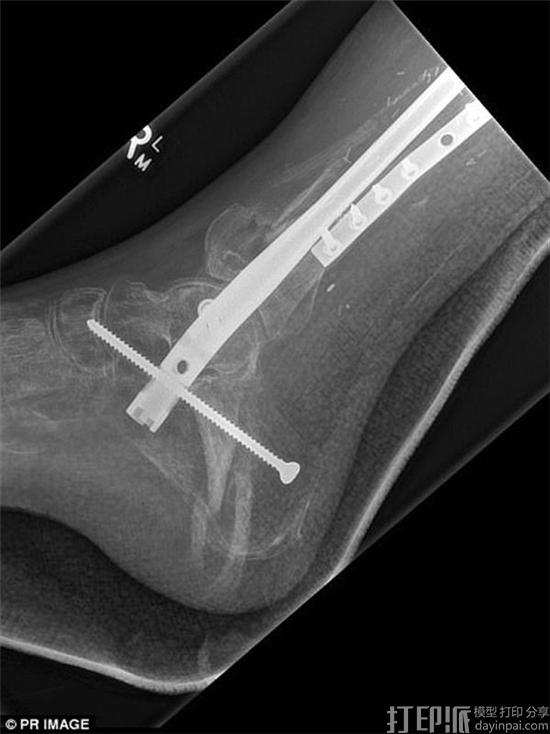

据了解,手术所用的3D打印胫骨支架长36厘米,是由昆士兰科技大学设计,然后在新加坡使用生物降解型聚合物材料制造的。手术之前,医生们用血管和取自Lichter的胫骨组织将其包裹,而手术时,这些组织已经开始生长。所以最终,如果一切顺利,这些组织便会长成全新的胫骨。

虽然手术能否彻底解决问题尚无法断定,但毫无疑问,它还是带给了Lichter希望,至少他不用再担心被截肢了。目前,Lichter恢复状况良好。而据医生透露,如果一切顺利,再过18个月他就可以正常行走了。

值得一提的是,这是全球首例3D打印胫骨支架植入手术,而Lichter也因此成为了世界首个接受此类手术的人。另外在手术之前,医生们就一直用羊进行着活体实验。所以这次,他们才有信心为Lichter实施手术。